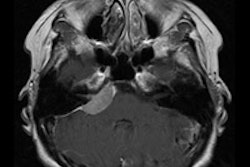

The survey asked radiologists how they would handle 12 incidental CT findings in a hypothetical 45-year-old woman with no history of malignancy (JACR, November 2011, Vol. 8:11, pp. 762-767).

The dozen findings included a 1-cm thyroid nodule, a 5-mm noncalcified lung nodule, coronary artery calcification, a 2-cm adrenal nodule, a 2-cm pancreatic cyst, a 1-cm enhancing liver lesion, a 2-cm high-density renal cyst, short-segment small bowel intussusception, a 1-cm splenic cyst, focal gallbladder wall calcification, and a 3-cm ovarian cyst in both a premenopausal woman and a postmenopausal woman, according to the authors.